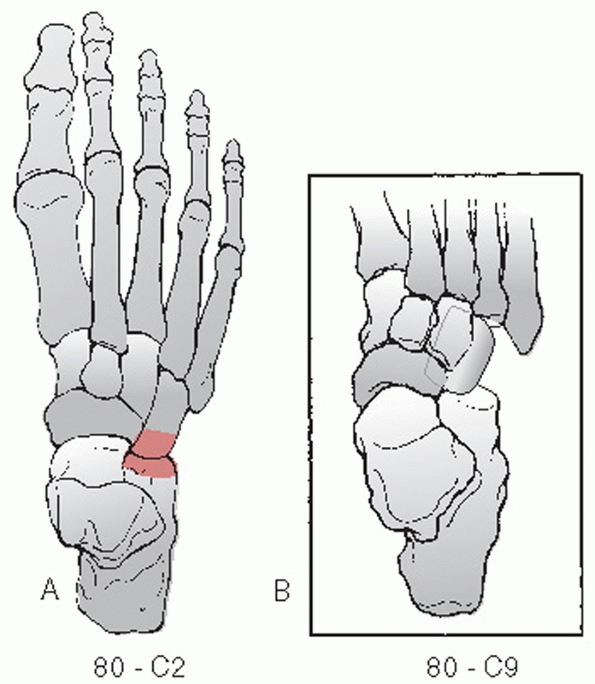

compendium identifies these injuries as 80-C2 when it involves the

all the joints would be designated 80-C9 (Fig. 60-14).

![]() |

FIGURE 60-14 OTA Classification of cuboid dislocations (80-C). A.

Isolated calcaneal cuboid dislocation. Isolated cuboid metatarsal dislocations are classified as a tarsometatarsal dislocation. B. True complete cuboid dislocation. |